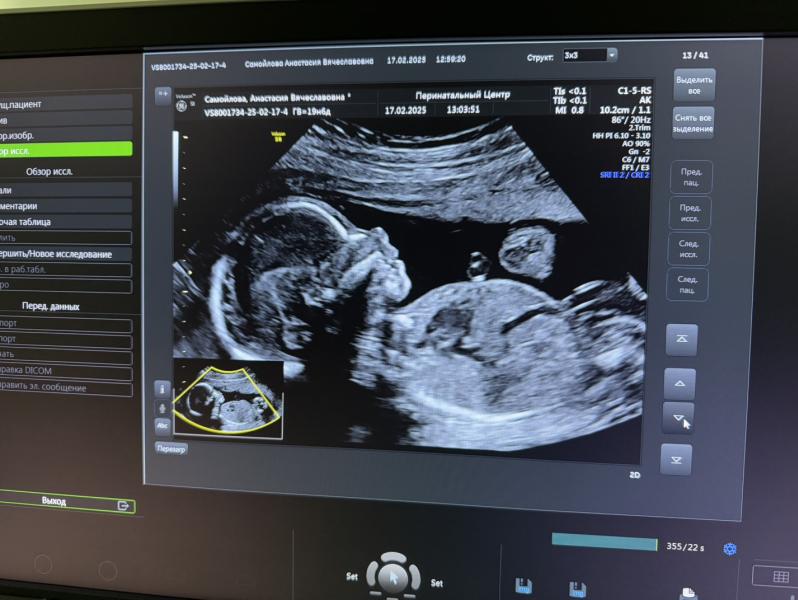

Наша малышка 😍

Прошли 2-й скрининг, как всегда на отлично!))

Вес примерно 330г., ноги за головой🙈 гимнастка) 🤸♀️

оба узиста (была сегодня платно в клинике и бесплатно в перинатальном) отметили очень красивый нос 🙈